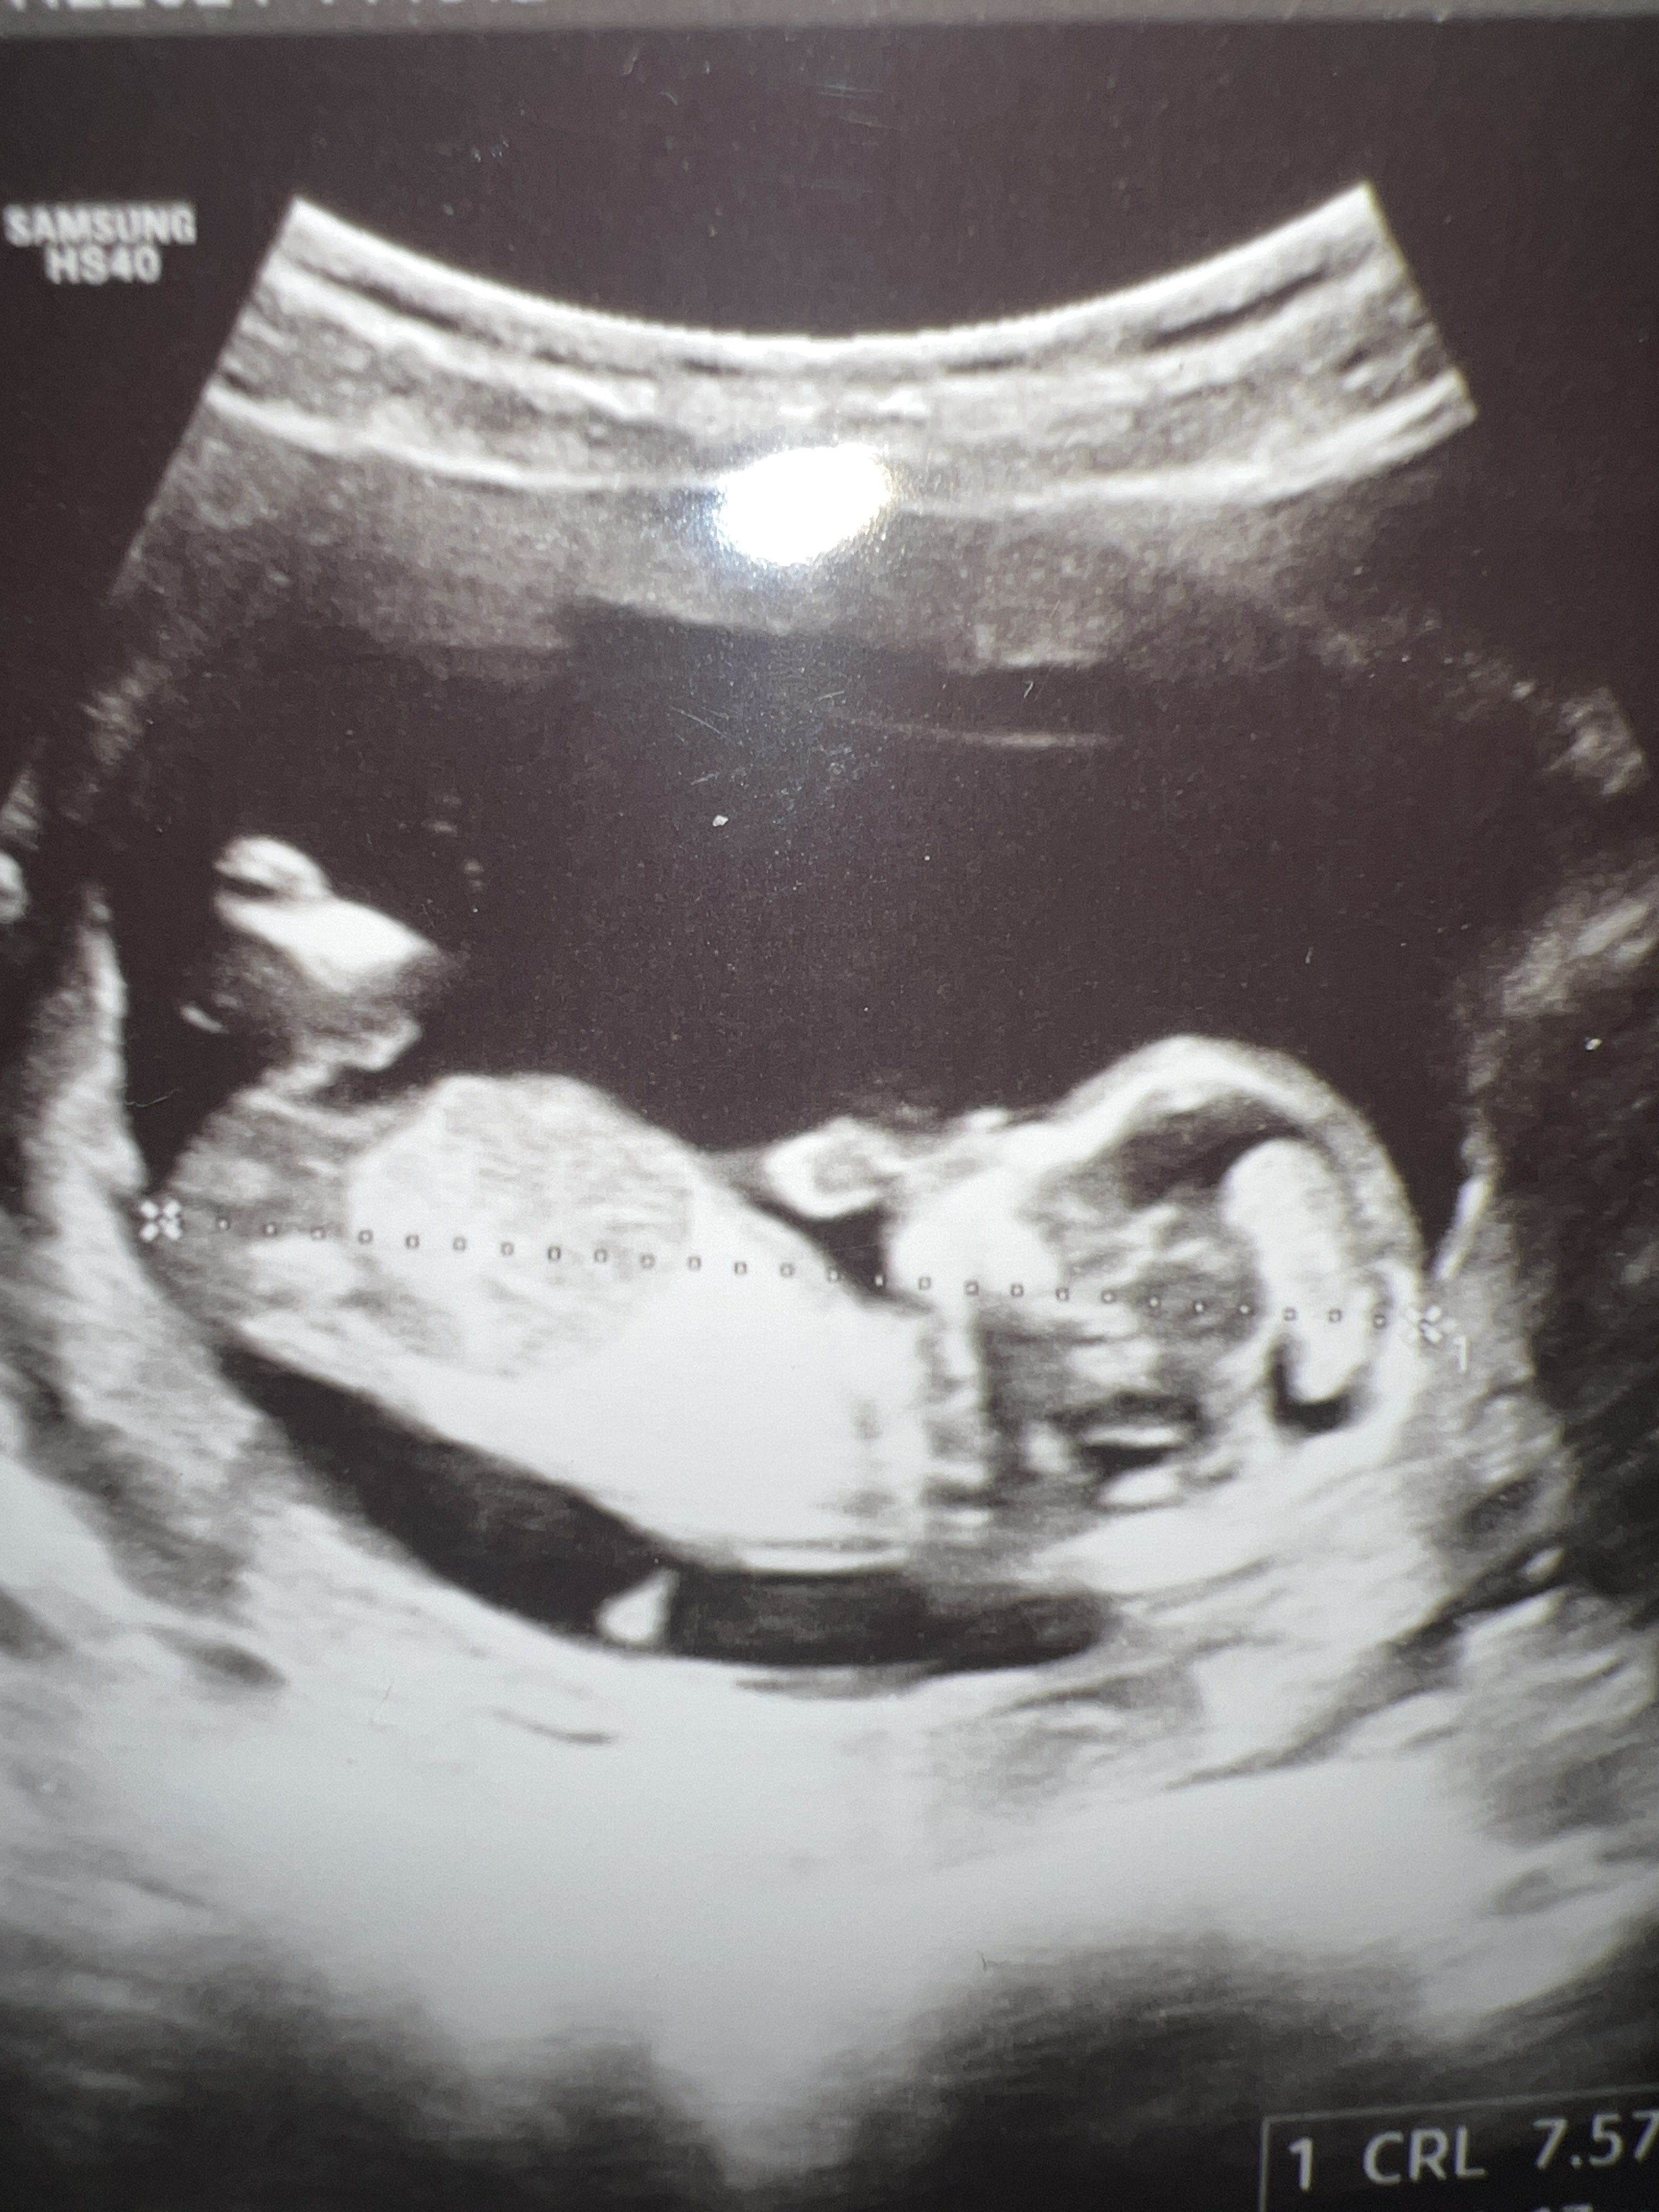

Na tym zdjęciu nie widać wyrostka, więc trudno powiedzieć, natomiast płeć z pierwszych prenatalnych często się zmienia, zwłaszcza w tę stronę że z dziewczynki okazuje się chłopczyk. Margines błędu w ocenie na tak wczesnym etapie jest spory.Hej dziewczyny, czy tu coś widać? Lekarz na prenatalnych powiedział wstępnie dziewczynka. A kilka dni później prowadząca ciążę że wygląda na chłopca.![]()